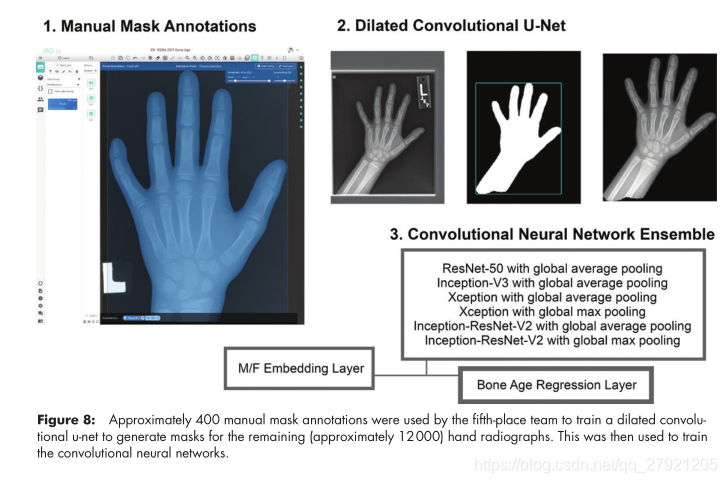

第五名: Leon Chen-MAD=4.527

特点:标注了400张手掌掩膜,训练了一个UNet网络,再对训练集进行分割,最后基于掩膜进行骨龄预测,其中还使用了年龄回归和性别嵌入层。